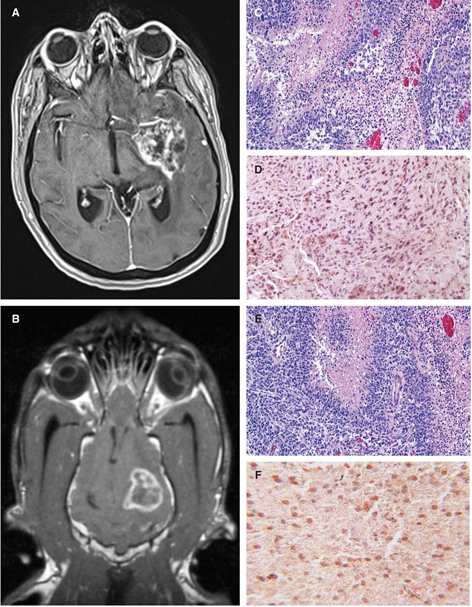

In parallel with advancements made in humans, non-human primates, and other animal models, we have been working toward the use of TcFUS for thermal ablation of canine tumors and focused disruption of the blood–brain barrier to facilitate drug delivery to the canine brain (109). The preclinical evaluation of TcFUS in dogs has posed additional and unique challenges. The tremendous inherent variations in skull size, conformation, and thickness within and among dog breeds has required expanding and refining engineering solutions developed to reliably achieve transcranial beam focusing. Although beam focusing aberrations associated with skull variability can be corrected using large arrays of individually controllable transducing elements, the geometry of existing FUS hemispheric arrays and the size and conformation variability, as well as positioning constraints of the canine cranium within these arrays complicates treatment delivery in the dog (Figure 5). Using computed tomographic scans of the head obtained prior to treatment co-registered with diagnostic MR data sets and a customized multi-element elliptical array, we are in the process of optimizing patient and canine species-specific phase offset simulations to correct for differences in acoustic wave propagation associated with skull heterogeneity, and to allow for electronic steering of the focal position.

Figure 5 Evaluation of TcFUS instrumentation in the canine model. Canine skull (A) positioned in the Exablate platform (InSightec Ltd., Dallas, TX, USA) hemispheric transducer array. In the background, an additional Exablate hemispheric transducer and couch are visible illustrating the equipment configuration that would be used to treat a human brain. Canine positioned on the RK-100 couch (FUS Instruments, Toronto, Ontario, Canada) system in preparation for transport into the MR suite for TcFUS BBB opening. Note the size difference in the transducers between the two systems (B, inset).

We have also attempted transcranial BBB opening in the normal canine brain using existing FUS systems (Figure 5). In our preliminary studies in dogs, we observed that the assessment of BBB opening using passive cavitation detection (PCD) resulted in considerable variability that was poorly associated with other measures of BBB opening, such as the opening volume (110). This is in contrast to findings indicating that PCD is an acceptable surrogate of BBB permeability in rodent models. We believe that these differences may be attributable to the gyrencephalic structure and increased white/gray matter, vascular, and ventricular heterogeneity of the canine brain compared with rodents, as other investigators have demonstrated similar PCD variability when using a non-human primate model (100). Optimization of PCD monitoring remains a focus of our current canine TcFUS work, and will be paramount to answering questions associated with quantifying drug delivery and efficiency that are fundamental to assessment of TcFUS in the canine brain tumor model, and translation of these drugs and technologies to humans.